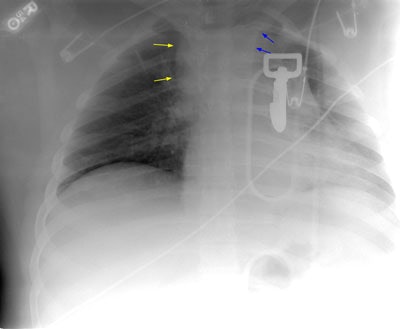

The plain film was a limited exam, but findings which suggested an aortic injury included: Loss of the contour of the aortic arch, A-P window opacification, a left pleural cap (blue arrows), and a soft tissue fullness in the right paratracheal region (yellow arrows). Click image to enlarge.